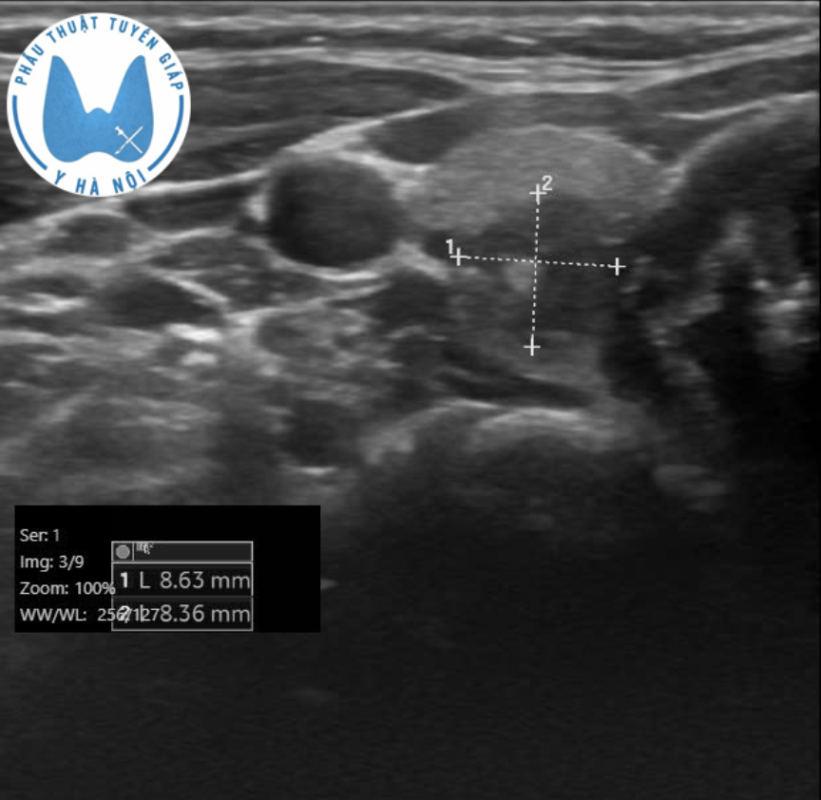

Siêu âm cho thấy một nhân tuyến giáp TIRADS 4, kích thước khoảng 2 cm, chưa có dấu hiệu xâm lấn xung quanh. Tuy nhiên, hình ảnh cũng ghi nhận một hạch cổ nghi ngờ di căn. Kết quả chọc hút tế bào kim nhỏ sau đó xác định: ung thư tuyến giáp thể nhú.